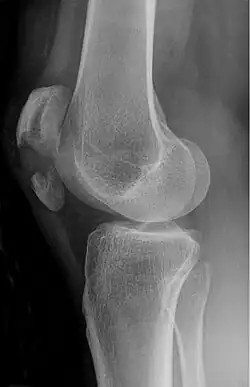

| A fracture of the patella seen on a lateral view | |

Patella fracture

A patella fracture is a break of the kneecap.[1] Symptoms include pain, swelling, and bruising to the front of the knee.[1] A person may also be unable to walk.[1] Complications may include injury to the tibia, femur, or knee ligaments.[2]